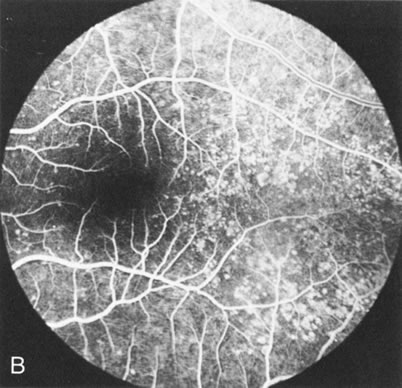

In Stargardt's disease, thes most common hereditary macular dystrophy, FA has a variety of functions. In the mildest fundus presentation, with visual symptoms and visual function out of proportion to the observed maculopathy, FA can confirm or even make the diagnosis and can avoid a mistaken diagnosis of malingering, hysteria, or central nervous system disease (Fig. 9A and B). When a maculopathy is present without surrounding parafoval flecks, FA may show patchy areas of transmission hyperfluorescence in the posterior pole, indicating a more diffuse involvement (Fig. 9C and D).

Fig. 9. Stargardt's disease–fundus flavimaculatus. The mild maculopathy (without parafoveal flecks) (A) is confirmed by the angiogram (B). The relative absence of the underlying choroidal flush, resulting in an easier visualization of the overlying retinal capillary circulation, has been referred to as the “silent” or “dark” choroid, and is considered a common finding in this disease. The diagnosis is confirmed in an individual with a pigmentary maculopathy without flecks (C). Here the angiogram demonstrates widespread transmission hyperfluorescence and a “silent” or “dark” peripapillary area (D). When the posterior pole shows multiple yellowish-white flecks (E), the angiographic findings do not necessarily correspond to the flecks (F). It should also be noted that despite the widespread abnormalities, the background choroidal fluorescence is normal.

In a large majority of patients (86% in one study),20 there is an absence or decrease in the background choroidal fluorescence (which is referred to as the “silent” or “dark” choroid) (see Fig. 9B). This warrants special attention because it occurs so frequently, is rarely found in other retinal disorders,21 and may be related to histopathology that shows an increase in lipofuscin in the RPE.22